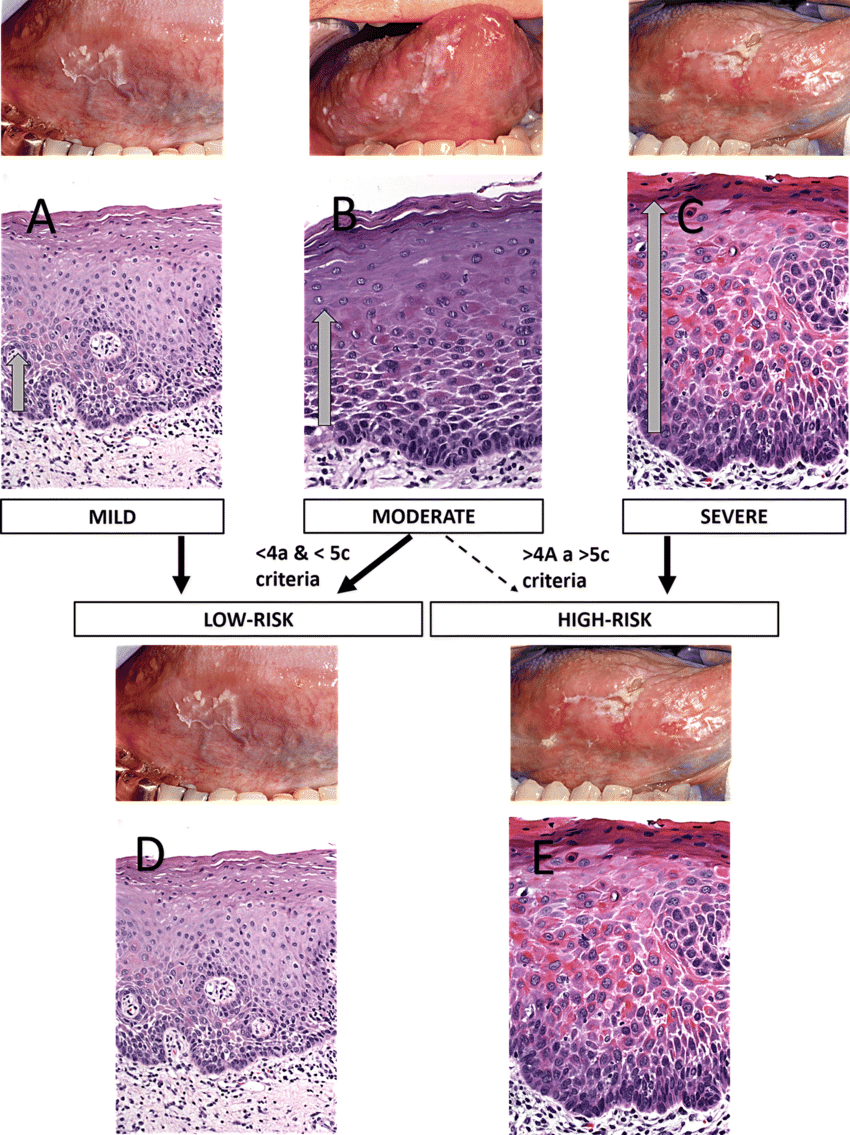

Oral epithelial dysplasia (OED)

- 分為三個程度

Mild

- 影響到下三分之一

- Basal cell 增生,變大

- Rete ridge 變寬

- 底層 keratin (紅染)

- 可能發炎

Moderate

- 到中三分之一

Sever